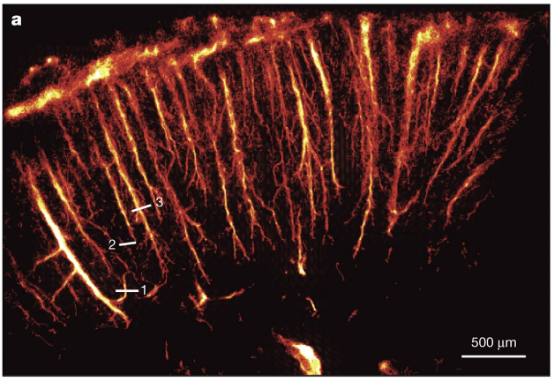

fUS是一种支持动物实时脑功能成像的新方法,相关方法与应用研究已有近40篇论文发表于Nature、Nature子刊、Science子刊、Cell、PNAS、Neuron等高水平期刊。fUS有望在神经科学基础研究、药理学与药物研发、中风与神经血管成像等领域发挥重要作用。

Iconeus One 是世界首款基于功能性超声技术(fUS,functional ultrasound)设计的成像系统,支持自由活动动物脑功能实时成像及血流成像。

Iconeus One系统搭载多种专用成像探头,可对清醒或自由活动状态的小鼠、大鼠以及非人灵长类等动物进行全脑实时动态功能成像及血流成像、器官组织的结构及血流成像。可兼容电生理记录与光遗传学。时间分辨率10 ms,普通模式空间分辨率100 μm,超高分辨率模式空间分辨率10 μm。